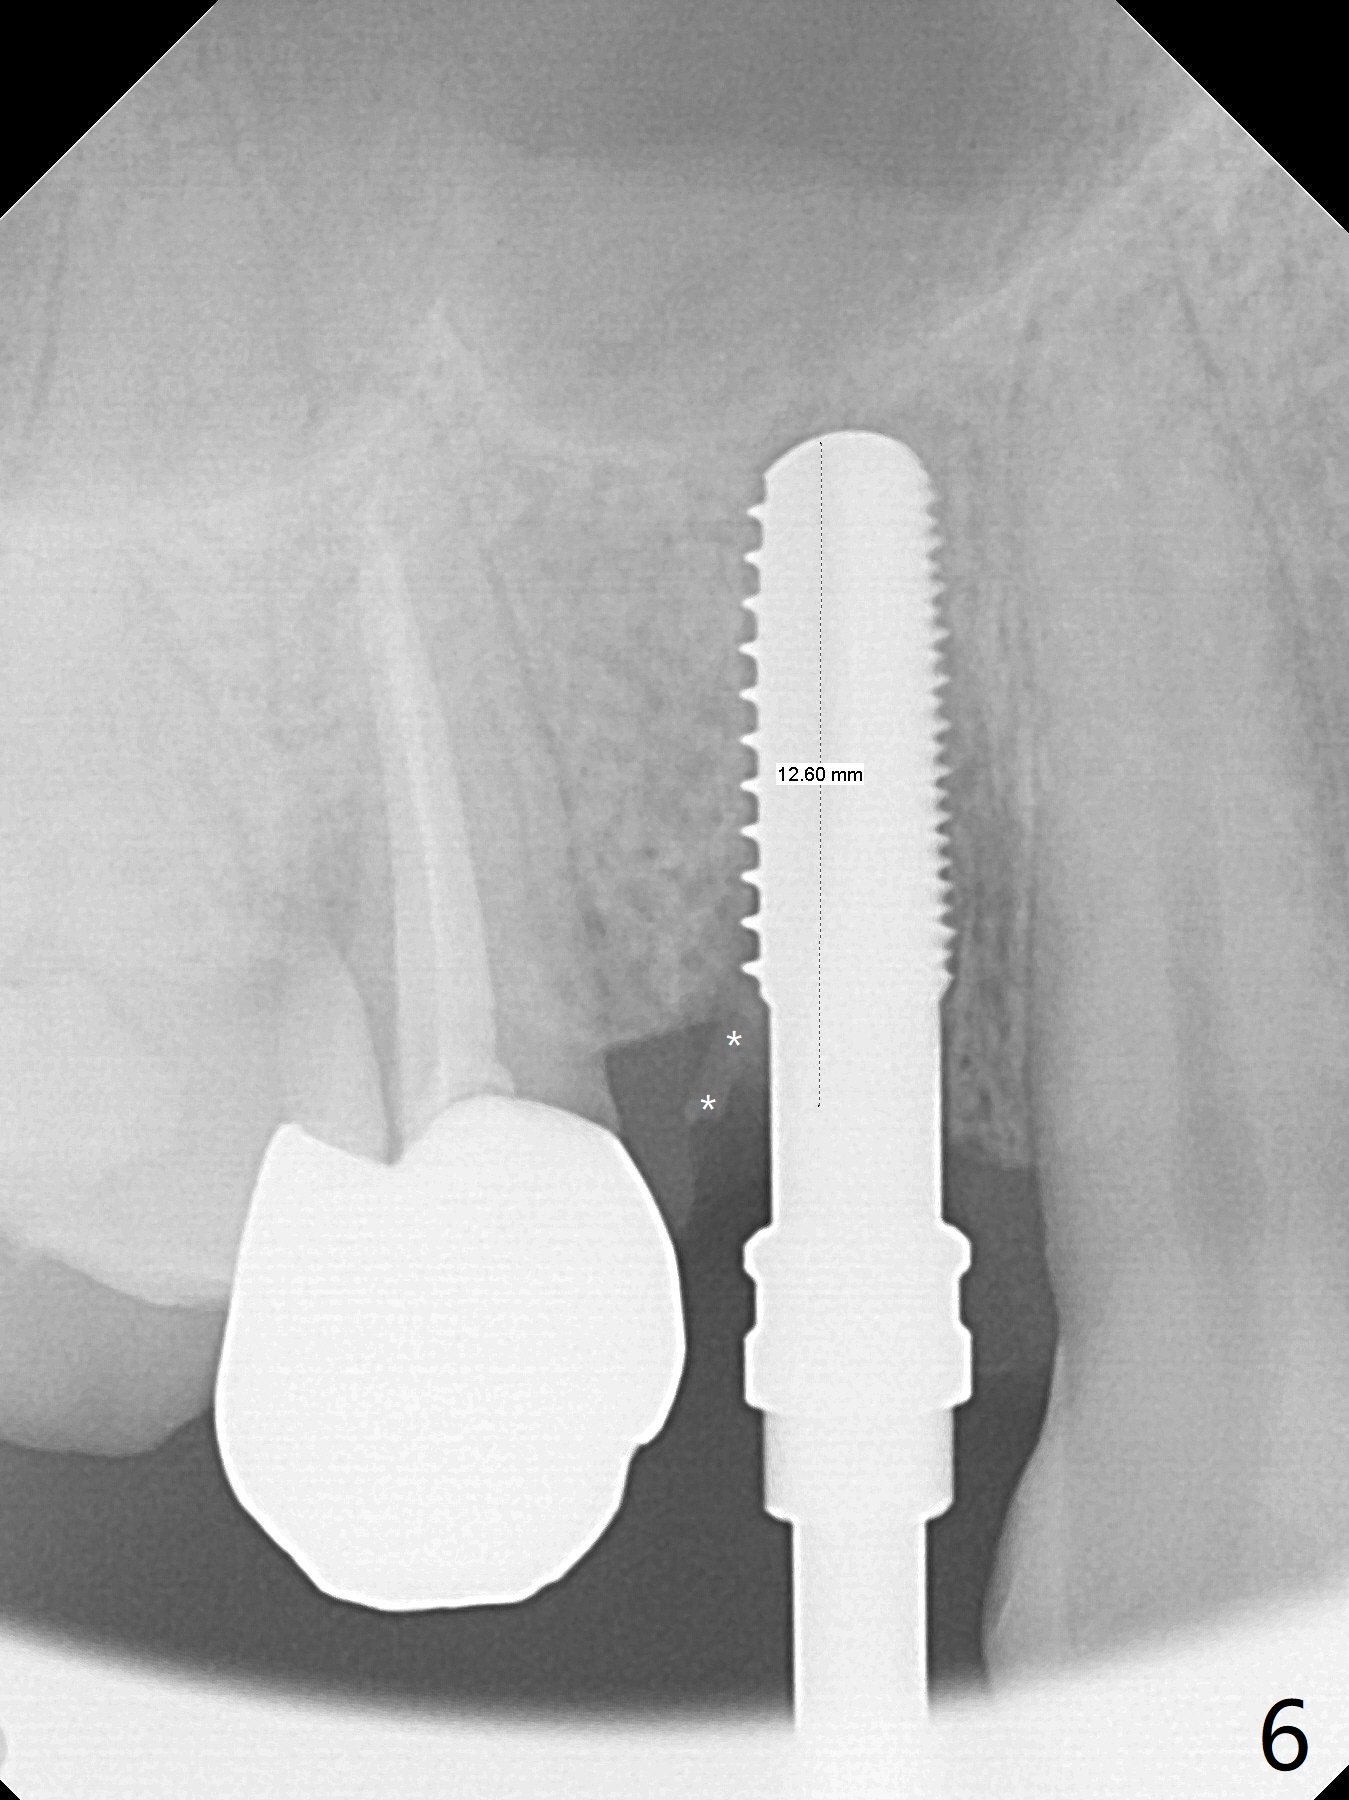

The buccal plate is normal at the tooth #5 (Fig.1) with the loose palatal fragment (Fig.2 P). Extraction leads to root fracture. Sectioning removes the palatal portion of the root and keeps the buccal semilunar piece (Fig.3 *); the mesiopalatal plate is resorbed (P). Initial osteotomy is off (Fig.4 (R: remaining root)). Redirection improves the trajectory (Fig.5). With the 2nd redirection (Fig.6 (4.5 mm tap)), a 4.5x12 mm implant is placed with 50 Ncm and sinus lift (Fig.7 black *); bone graft is placed with emphasis on the palatal defect (white *). As usual, an immediate provisional is fabricated. In fact the abutment may be not completely seated because of contact with the mesial crest. Prepare anesthetic and 5.5 mm profile drill. Take parallel BW or PA. Take occlusal photos to show no buccal or mesiopalatal atrophy. After 5.5 mm profile drill 11 months postop, the abutment has no contact with the mesial crest (Fig.8 <). Since the proximal contact between #3 and 4 is light with food impaction, the provisional at #5 is fabricated with tight distal contact. When the patient returns for final crown cementation (Fig.9), the food impaction is minimal between #3 and 4. The distal black triangle (Fig.10 *) and exposure of the abutment margin (^) are partially related to provisional fabrication and should dissolve over time considering socket shield.